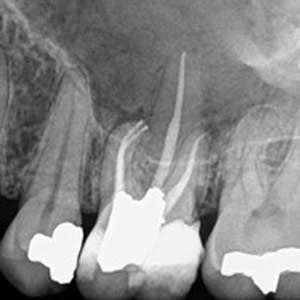

NON-SURGICAL

Oftentimes, our patients need non-surgical treatments that require minimal intervention. This intertwines with our belief that preventative maintenance and regular dental care can minimize the need for surgeries. You can rest assured that our highly trained and experienced team consistently provides the highest quality endodontic treatments and assistance available in the North Shore.